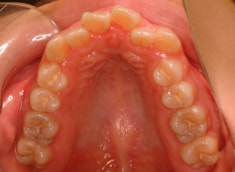

治療前